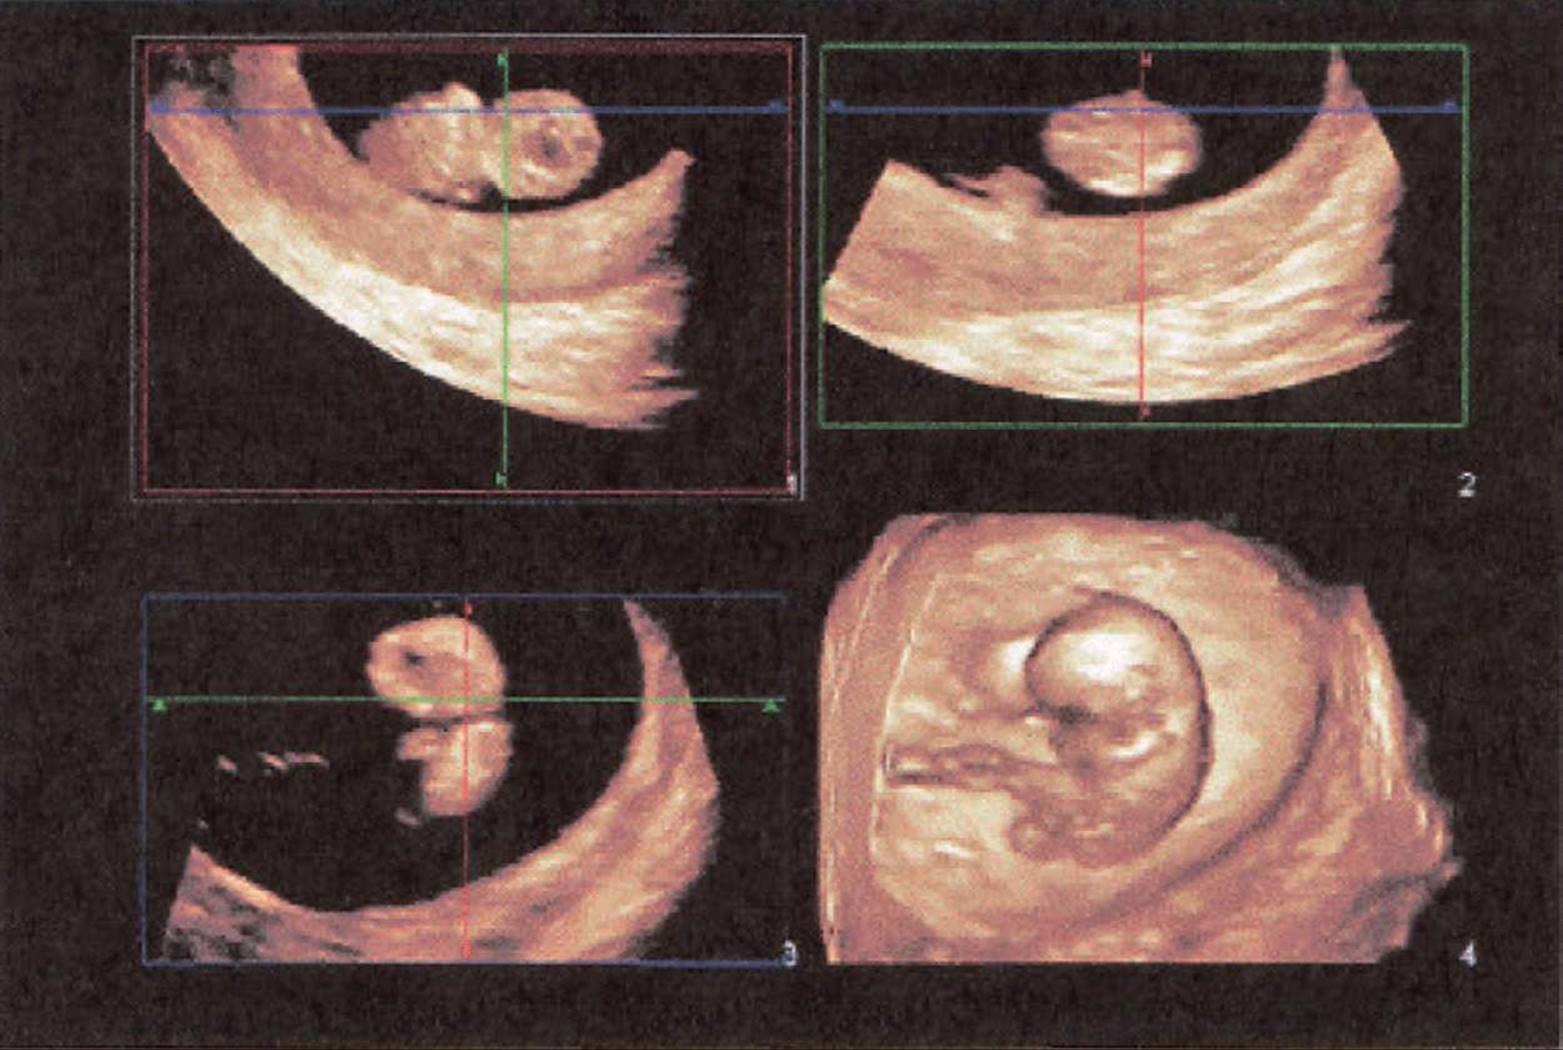

FIGURE 8–5. Three-dimensional sonogram of 10-week intrauterine pregnancy. (Courtesy of Philips Healthcare.): Top left: long axis showing fetal heart and trunk; Top right: short axis through bottom of left hand; Bottom left: coronal plane; Bottom right: 3D volume with surface rendering showing the entire fetus and umbilical cord.